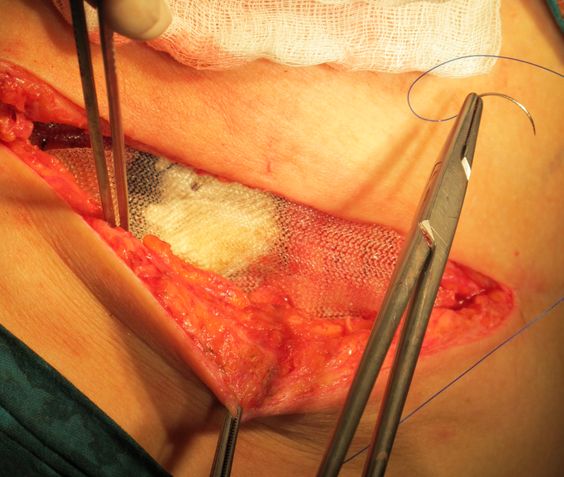

Пластика дефекта брюшной стенки проленовой сеткой.

Ушитая операционная рана.